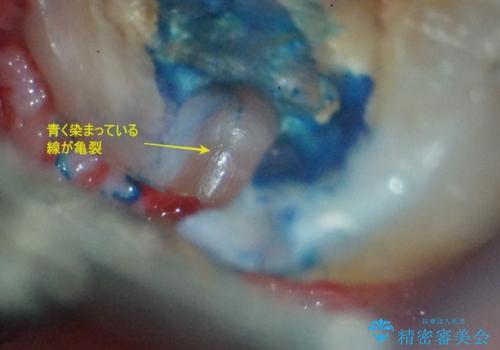

破折の深さが歯根まで及んでいたため抜歯を行いました。

根っこのところまで歯が割れていたため、歯を残すことは不可能と診断し抜歯後、インプラントで治療を行いました。